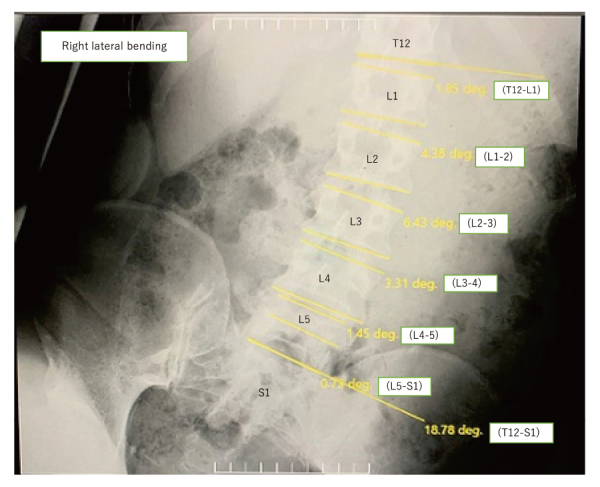

[目的]本研究的目的是明确不同性别和年龄组的腰椎侧弯运动相关活动范围的初步参考值。[方法] 研究对象为 82 名无腰背痛的志愿者,包括 16-19 岁至 80-89 岁年龄组各 5 名男性和 5 名女性。所有受试者都接受了腰椎侧屈的X光片检查;从T12到骶骨的椎体侧屈范围(ROLB)由三名观察者测量两次。[结果]所有受试者的整个 T12-S1 脊柱的 ROLB 与年龄呈显著负相关(P < 0.01)。女性腰椎的 ROLB 往往更大,16-19 岁和 70-79 岁之间的差异有统计学意义(P < 0.05)。每个椎节的侧屈角度在L3-L4最大,在L5-S1最小(0.7°)。[结论]按性别和年龄组对腰椎侧屈参考值进行了研究;L3-L4的侧屈角度最大,年龄越大,侧屈角度越小。

[Purpose] The purpose of this study was to clarify the preliminary reference values for the lumbar spine range of motion associated with lateral bending exercises by gender and age group. [Methods] Subjects were 82 volunteers without low back pain, including five males and five females in each age group from 16-19 to 80-89 years. All subjects underwent radiographs of the lumbar spine with lateral flexion; the range of lateral flexion of the vertebrae from T12 to the sacrum (ROLB) was measured twice by three observers. [Results] The ROLB of the entire T12-S1 of all subjects showed a significant negative correlation with age in both sexes (p < 0.01). The ROLB of the lumbar spine tended to be greater in females, with a statistically significant difference between those aged 16-19 and 70-79 (p < 0.05). Lateral flexion angles for each intervertebral segment were largest at L3-L4 and smallest at L5-S1 (0.7°). [Conclusion] Lumbar ROLB reference values were examined by gender and age group; ROLB was greatest in L3-L4, and ROLB tended to be lower in older age groups.